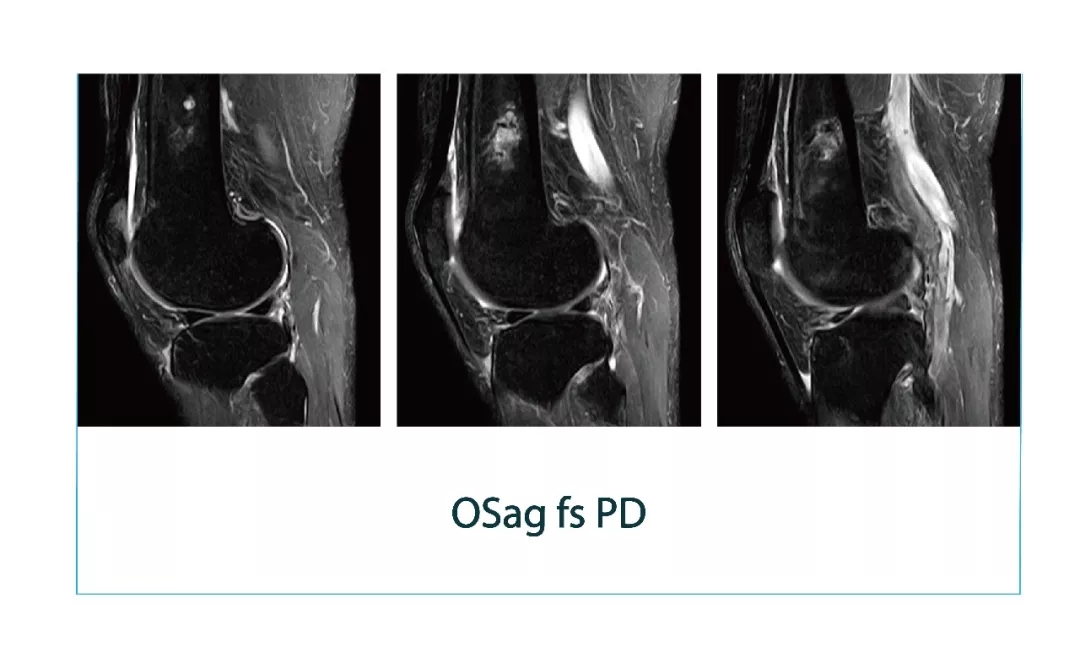

【朗润影像档案】磁共振影像病例分享(编号20180112)